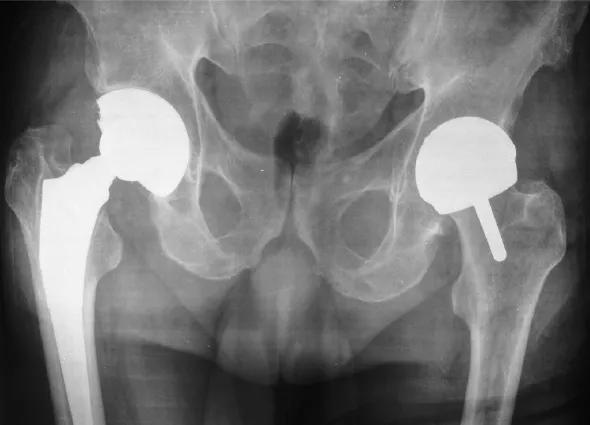

One total hip replacement; one hip resurfaced

While THA involves removing the entire femoral head and neck and replacing it with a ceramic head and long metal stem set deep into the femur, hip resurfacing requires removing only a few millimeters of bone from the femoral head. It is then covered with a metallic cap attached to a smaller stem drilled into the bone.